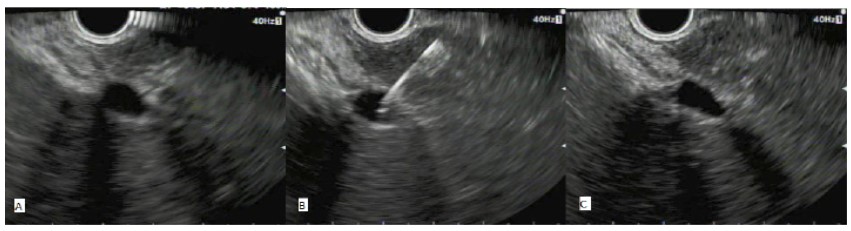

Figure 1: EUS Guided Portal Venous Sampling Sequence.

(A): With the tip of the echoendoscope located along the lesser curvature of the stomach (mid-body) the main portal vein is located. This is followed to the right and left portal vein bifurcation and the intra-hepatic left branch is targeted for fine needle aspiration.

(B): Using the distance function, we ensure a 1-1.5cm segment of hepatic tissue is between the needle insertion site and the vein. A 22G FNA needle is used to puncture the left main branch of the portal vein and the stylet withdrawn for sampling.

(C): After the needle is withdrawn the site is reassessed under EUS to check for immediate bleeding.